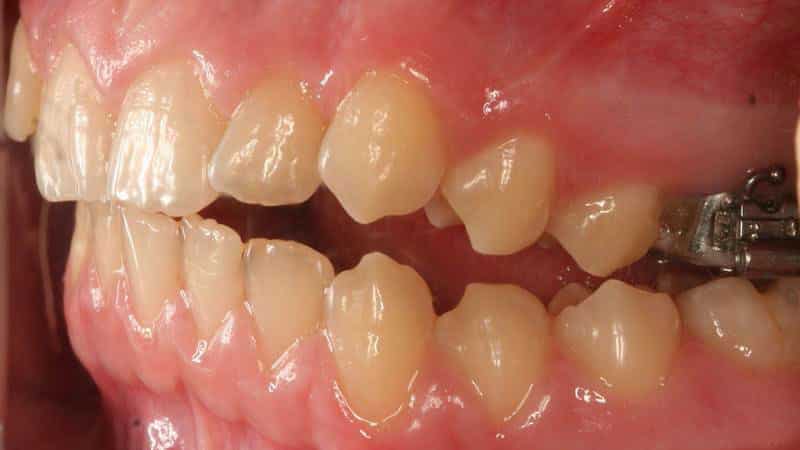

Перекрестный прикус может возникнуть не только в детском возрасте, но и у взрослых. Лечение данной аномалии у взрослых обычно включает использование ортодонтических аппаратов. Эти специальные системы помогают корректировать форму зубной дуги, нормализовать работу жевательных мышц и правильно расположить нижнюю челюсть. Для исправления прикуса устанавливаются брекеты, а срок их ношения зависит от степени выраженности проблемы.

Если перекрестный прикус возник внезапно, возможно, потребуется хирургическое вмешательство. Операция также может быть необходима для тех, у кого данная патология имеет наследственный или врожденный характер.

После восстановления правильного прикуса крайне важно поддерживать достигнутый результат. Рекомендуется использовать ретенционные аппараты, такие как съемные пластины, которые надеваются на ночь. Все рекомендации врача-ортодонта следует строго соблюдать.

- Несъемные аппараты: К ним относятся брекеты и различные системы, которые фиксируются на зубах. Они обеспечивают более точное и постоянное воздействие на зубы и челюсти, что особенно важно для взрослых пациентов, у которых челюстной аппарат уже сформирован.